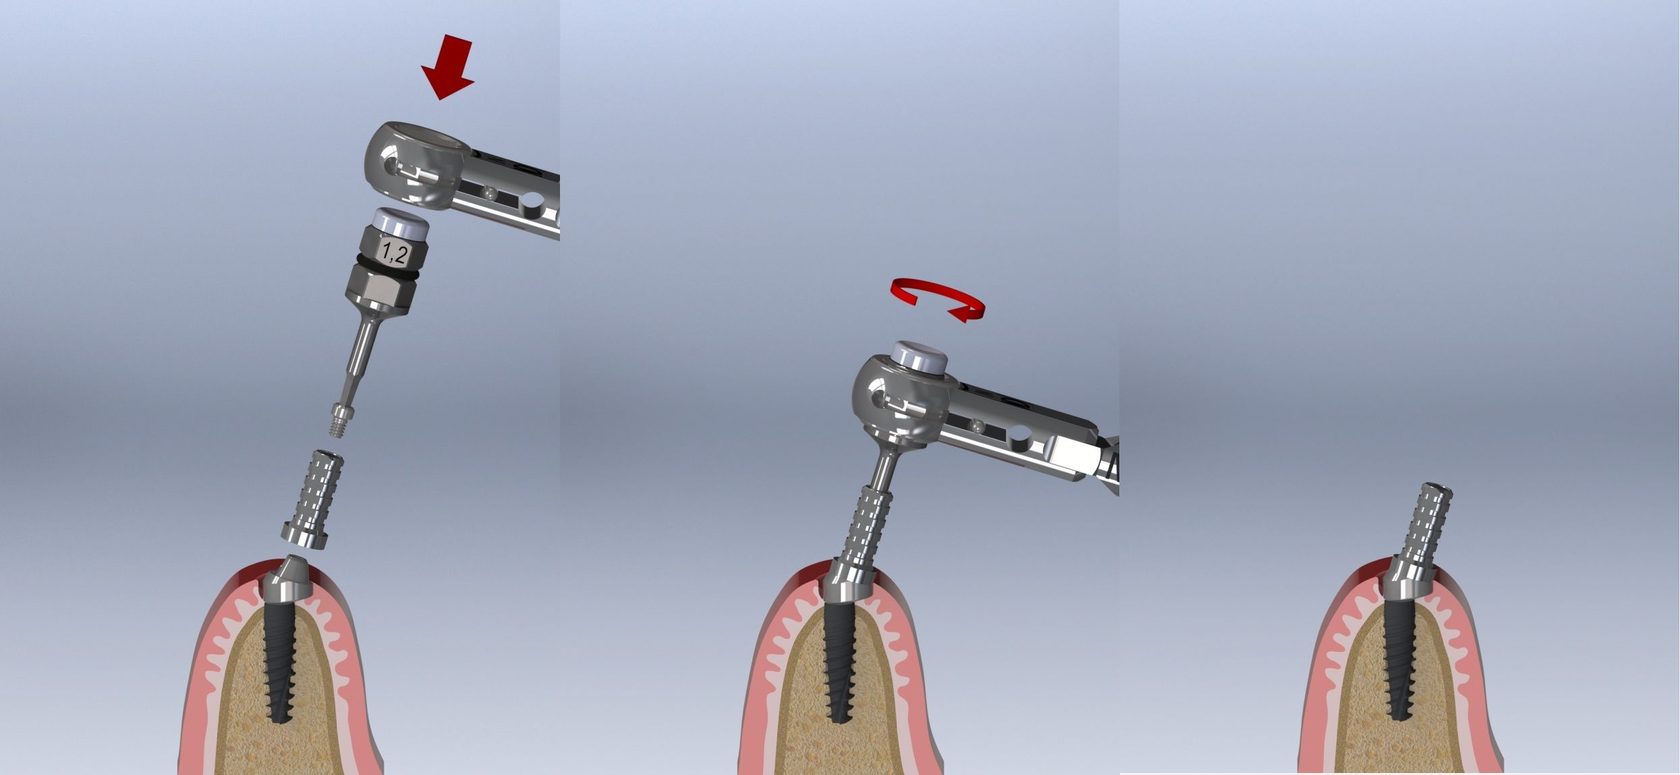

Пошаговое руководство по установке съёмного протеза на импланты